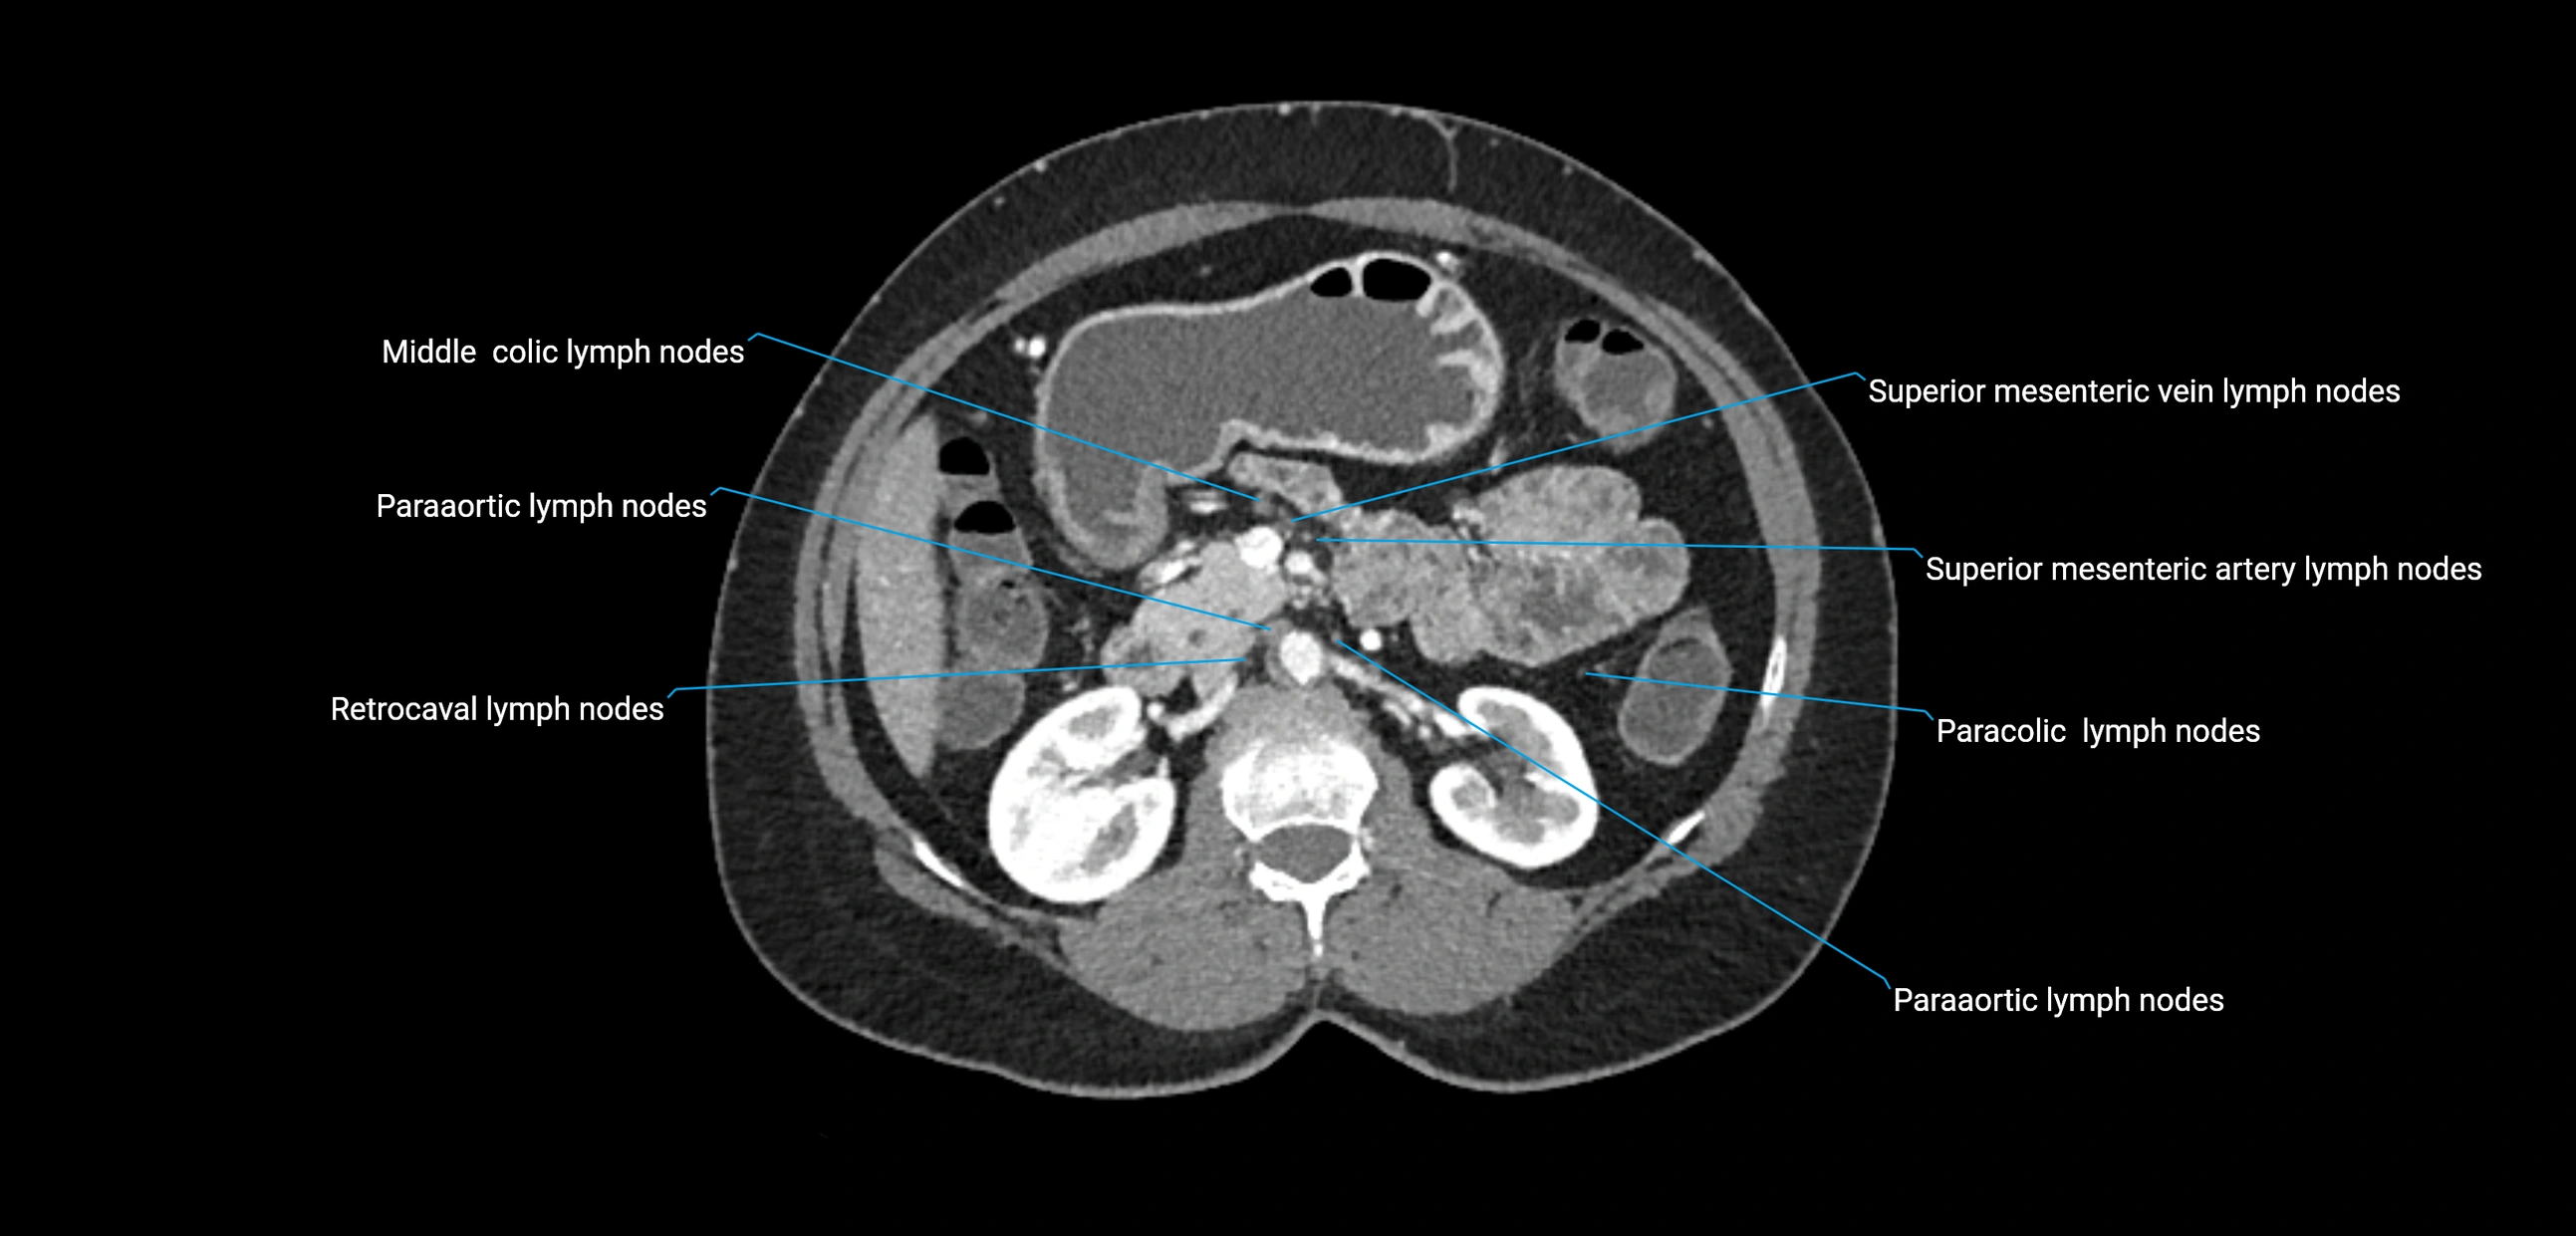

CT Appearance

CT Pre-Contrast:

• Nodes appear as soft-tissue density nodules adjacent to the aorta and IVC

• Calcification may be seen in chronic infections (e.g., tuberculosis)

CT Post-Contrast:

• Normal nodes enhance homogeneously

• Malignant nodes may show heterogeneous enhancement, central necrosis, or conglomerate formation

• Size >1 cm short axis is suspicious, though morphology and distribution are equally important

CT Venography (CTV):

• Demonstrates nodal encasement or compression of adjacent vessels (aorta, IVC, renal veins)

• Useful in staging testicular and ovarian malignancies

• Provides 3D reconstructions for retroperitoneal lymph node dissection planning

CT image

image